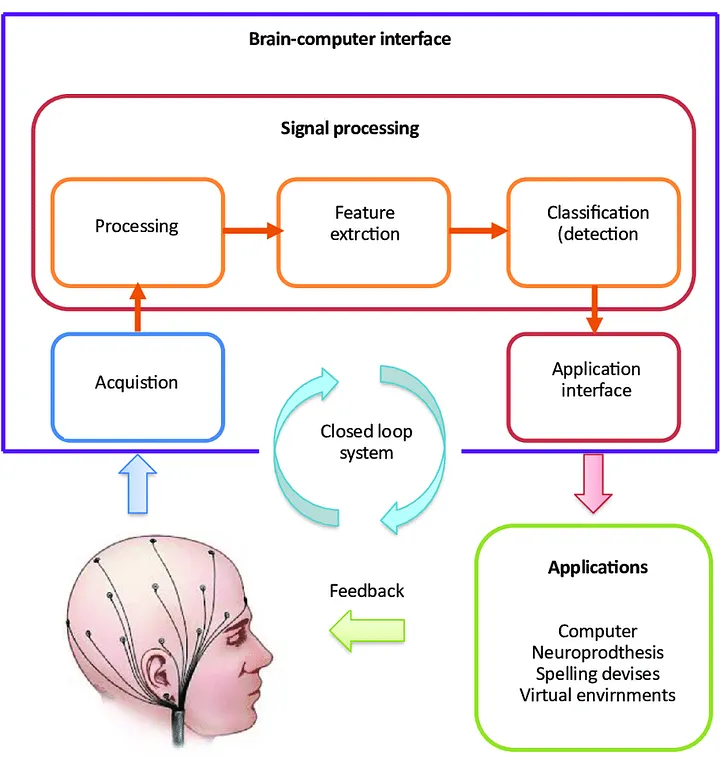

脑机接口是一种能解码大脑信号并将其转发到输出设备的设备,从而实现个人的预期功能。它有许多潜在的应用。Neuralink 和 ClearPoint Neuro 等公司一直致力于推动 BCI 的发展,使其能够用于假肢的运动,并将视觉想象转化为数字信号,应用领域非常广泛。那么,如果这项技术能够检测神经信号并以可视方式呈现,它是否能应用于疾病治疗呢?在跟踪认知功能进展和疾病转移方面,BCIs可以成为一种宝贵的工具。因此,临床医生可以就治疗策略做出明智的决定,从而实现以证据为基础、以患者为中心的护理。

脑机接口是如何工作的

脑机接口有4 个连续的组成部分:

信号采集:用于控制 BCI 系统的最常见信号是电信号。这就是输入。

特征提取:特征提取的目的是为电生理数据找到合适的表示方法(信号特征),以简化随后的分类或大脑模式检测。有许多特征提取方法可用于生物识别(BCI)系统,如振幅测量、频带功率、Hjorth 参数、自回归模型和小波。

特征转换/分类:分类器使用特征提取器记录的特征,将记录的信号样本归入大脑模式类别。

设备输出/应用界面:系统的反馈或输出最终被转化为可用于控制各种设备的适当信号。高级应用包括控制假肢设备和多媒体应用。

BCI的组成部分